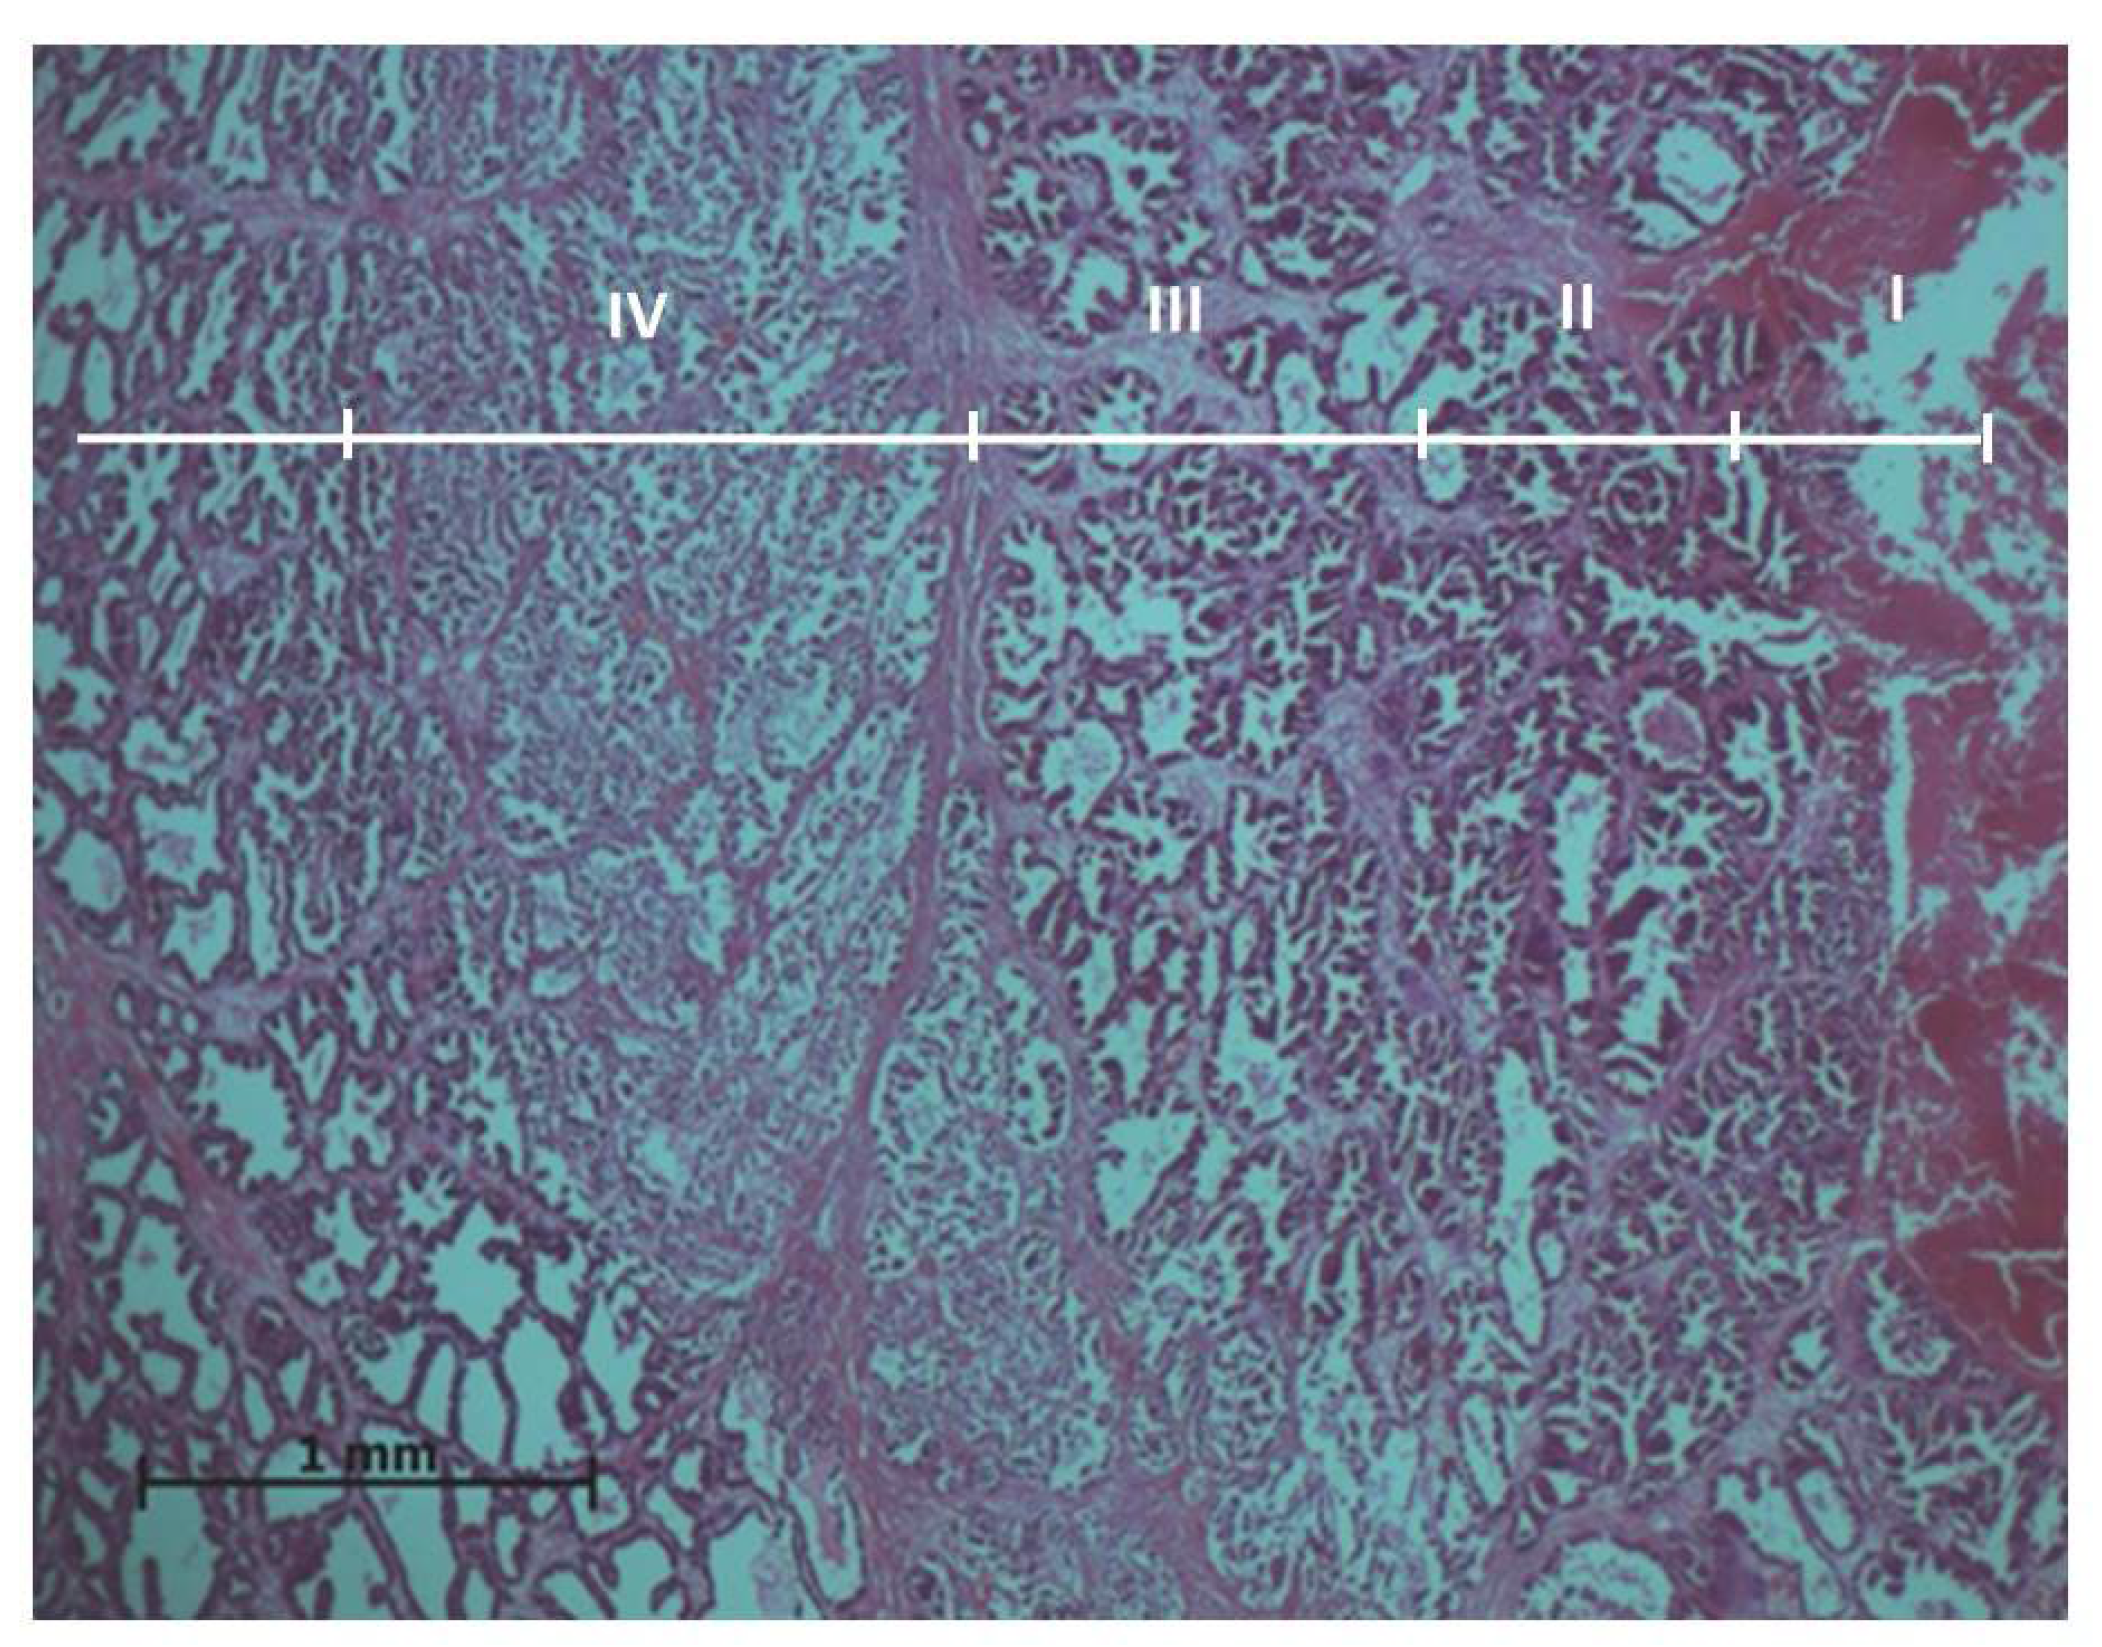

Experimental results showed that ablation effects on the prostate tissues vary going further from the active electrode. Thus, the histopathological evaluation of the prostate samples resulted in four exposure zones (Figure 1).

Figure 1.

General histologic image of the prostate after ablation: I—ablation site; II—application zone; III—necrosis zone; IV—transition zone. Microtome-cut sections of prostate samples were stained with hematoxylin and eosin.

In this experimental work, the effect of different RFA treatments (without cooling and with cooling by two NaCl salt solutions) on prostate morphological changes in the formed tissue damage zones (areas and perimeters) was evaluated and determined. The areas and perimeters of damage zones were also assessed, calculated, and compared. Based on this strategy, the four zones of histopathological tissue damage were identified (see Figure 1) as: zone I, which was in direct contact with the electrode; zone II (the application zone) that was adjacent to the thermal electrode (Figure 2); zone III was the necrosis zone (Figure 3); and zone IV was the transition zone (Figure 4). The latter tissue damage area extends beyond the lobe boundaries. The intact zone was observed around the transition zone and consisted of normal epithelium and stroma (see Figure 1 and Figure 5). Moreover, the ablation lesions formed following RFA in the prostate were similar to the lesions formed after RFA in another parenchymal tissue, the liver []. Thus, it was observed [] that after the RFA procedure zones of liver tissue damage were formed, these were identified as the central necrosis zone, the hemorrhagic marginal, and the transitional zones. It has been reported [] that after the ablation of the liver, hemorrhages with lymphocytic infiltrates occur in the tissue surrounding the necrosis zone, much like in the prostatic parenchyma after ablation procedures.